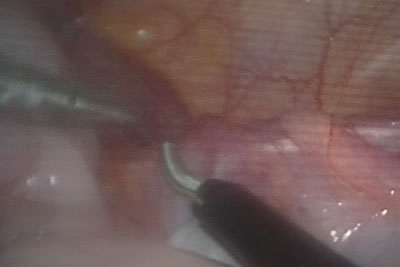

Коагуляция яичковых сосудов

Коагуляция яичковых сосудов.